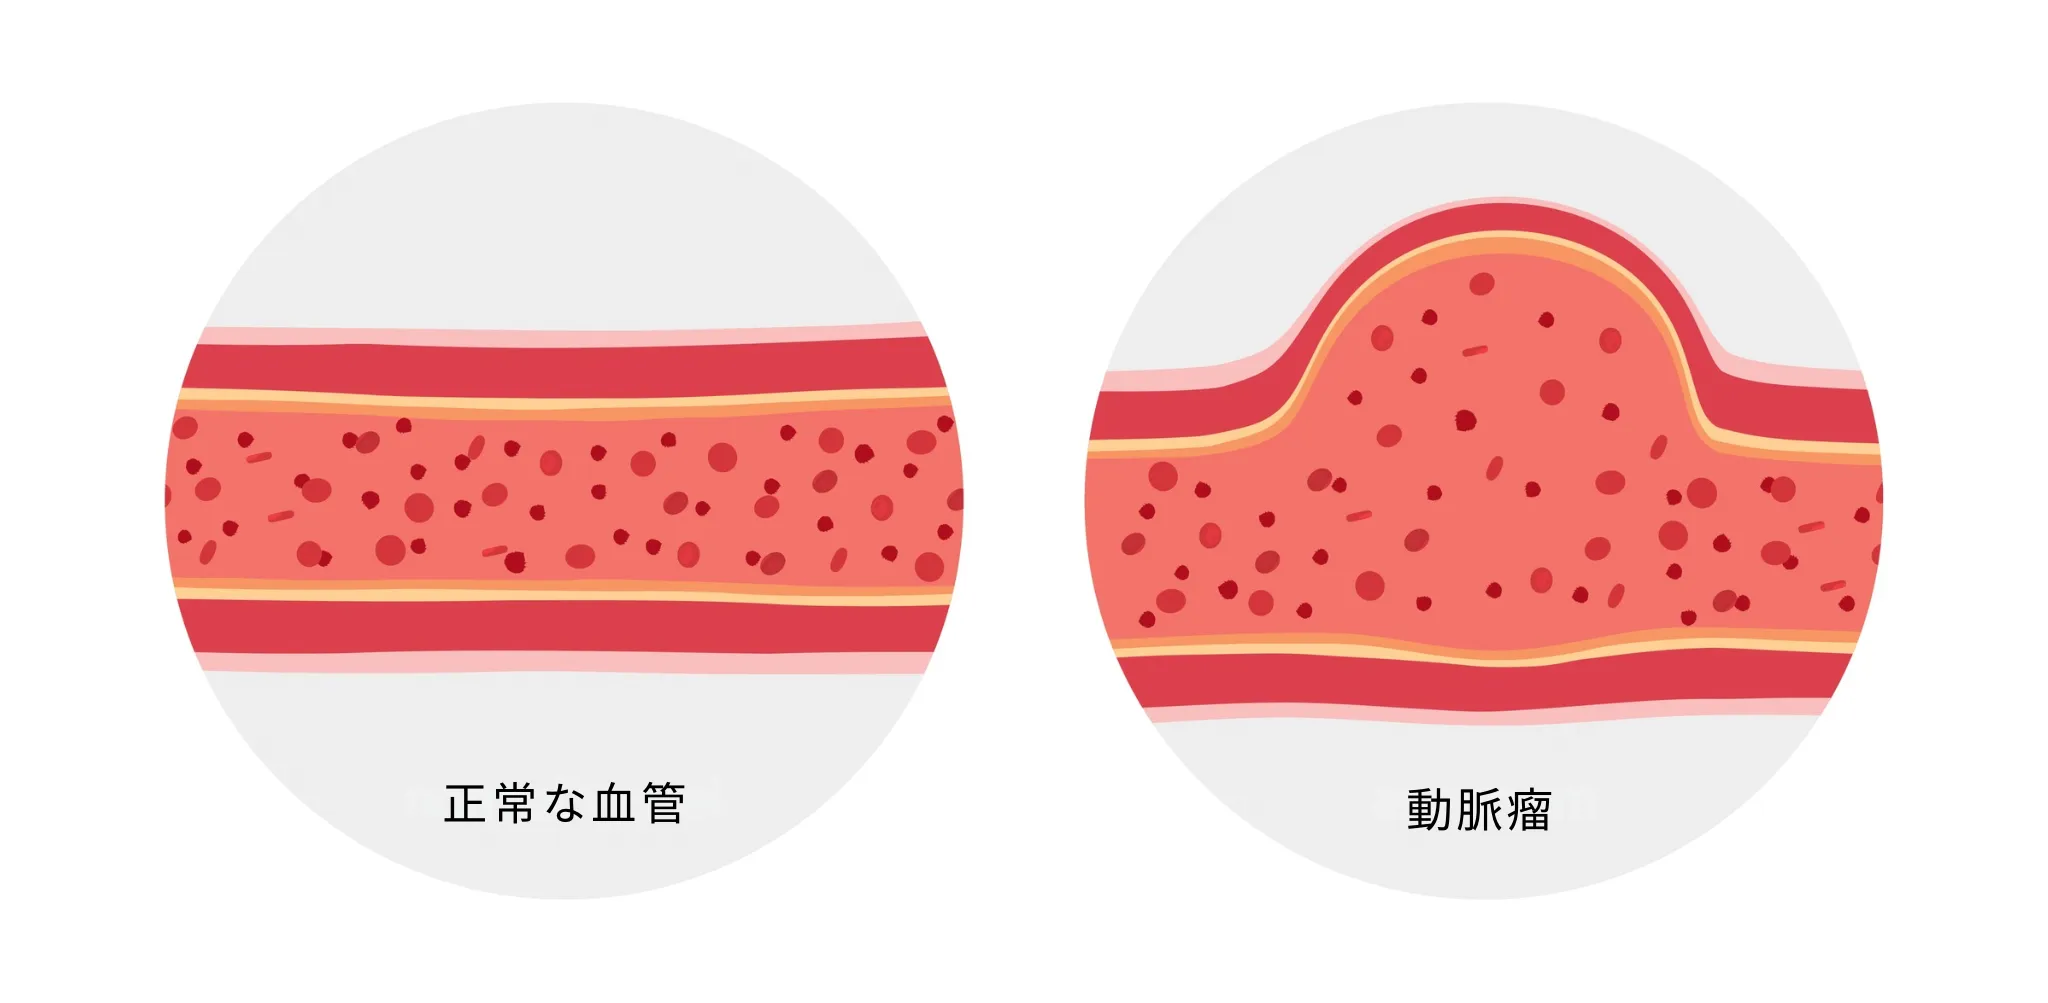

大動脈瘤

大動脈瘤は、動脈硬化などにより大動脈の壁が弱くなり、血管が風船のように膨らむ病気です。胸部大動脈瘤と腹部大動脈瘤があり、多くの場合は無症状で経過しますが、瘤が大きくなると破裂のリスクが高まります。破裂すると命に関わる緊急事態となるため、早期発見と適切な経過観察が重要です。

大動脈瘤は、多くの場合で無症状のまま経過します。健康診断の胸部X線や腹部エコー検査で偶然発見されることが多くあります。瘤が大きくなると、胸部大動脈瘤では声のかすれや飲み込みにくさ、腹部大動脈瘤では腹部の拍動を触れることがあります。大動脈瘤が破裂すると致死的な状態になるため、早期発見が重要です。

大動脈瘤が小さい場合は、定期的な画像検査による経過観察を行います。血圧管理や動脈硬化の進行を防ぐ治療も重要です。瘤が一定の大きさ(胸部大動脈瘤で5〜6cm、腹部大動脈瘤で5cm程度)になると、破裂のリスクが高まるため、手術治療が検討されます。

大動脈瘤と言われましたが、症状がありません。治療は必要ですか?

大動脈瘤は、小さいうちは無症状のことが多いですが、大きくなると破裂のリスクが高まります。定期的な画像検査で大きさを観察し、血圧管理や動脈硬化の進行を防ぐ治療を行うことが重要です。瘤の大きさによっては手術治療が必要になります。